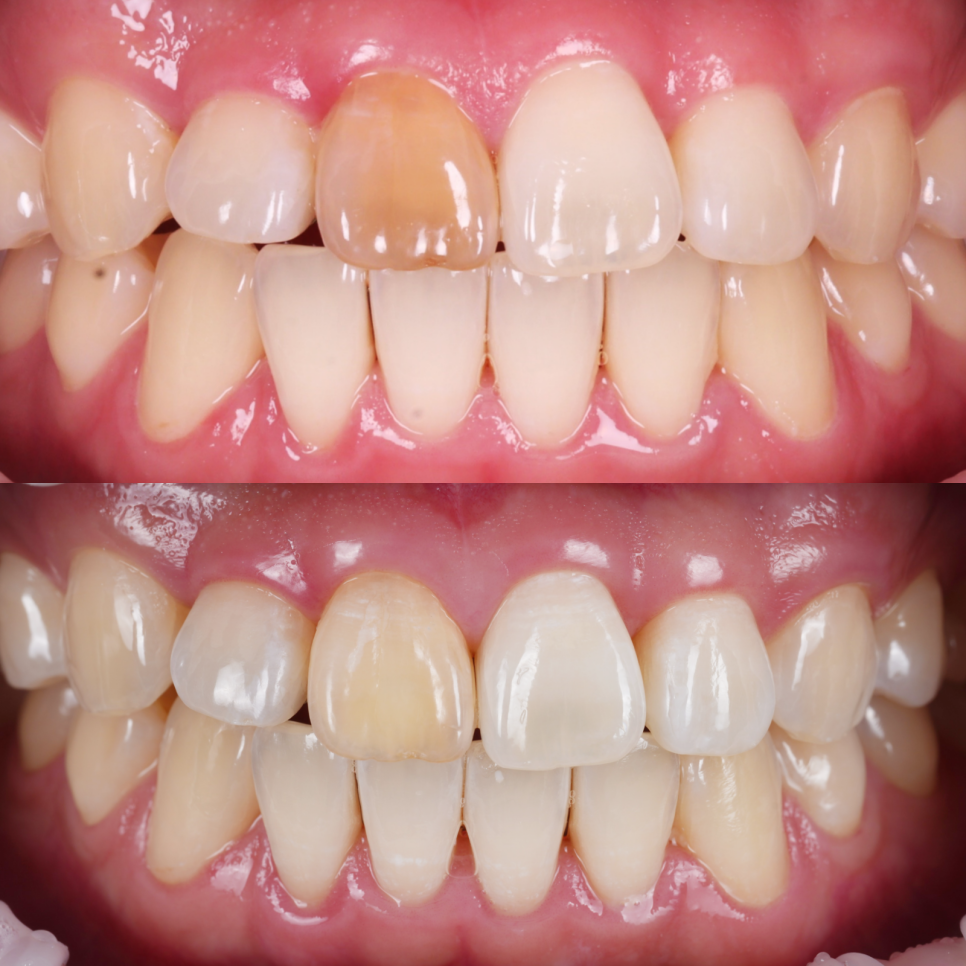

실활치 미백 전, 후 / 촬영일 : 250905 / 250926

최대한 밝게 만들어 놓은 상태에서

더이상 치아가 반응하지 않아

레진 비니어링(페이싱)을 하기로 했어요.

이때 중요한 것은 방습과 색 조화인데요.

저는 철저하게 러버댐을 장착해

침이나 습기로부터 차단했고

치아의 원래 색과 투명감을 재현하기 위해

여러 가지 색조의 레진을 겹겹이 적층했어요.

법랑질 특유의 투명감, 상아질의 따뜻한 톤,

그리고 빛이 닿을 때 생기는 halo 효과까지

하나하나 구현했죠.

환자분은 레진이라는 재료를 올렸을 뿐인데

마치 본래 치아가 되돌아온 것처럼

자연스럽게 보였어요.

이런 차이가 바로 ‘디테일의 힘’이라고 생각해요.

치료가 끝난 뒤 환자분은 거울을 들고

한참이나 치아를 들여다보셨어요.

촬영일 : 251001

촬영일 : 250905 / 250926 / 251001

촬영일 : 250905 / 251001